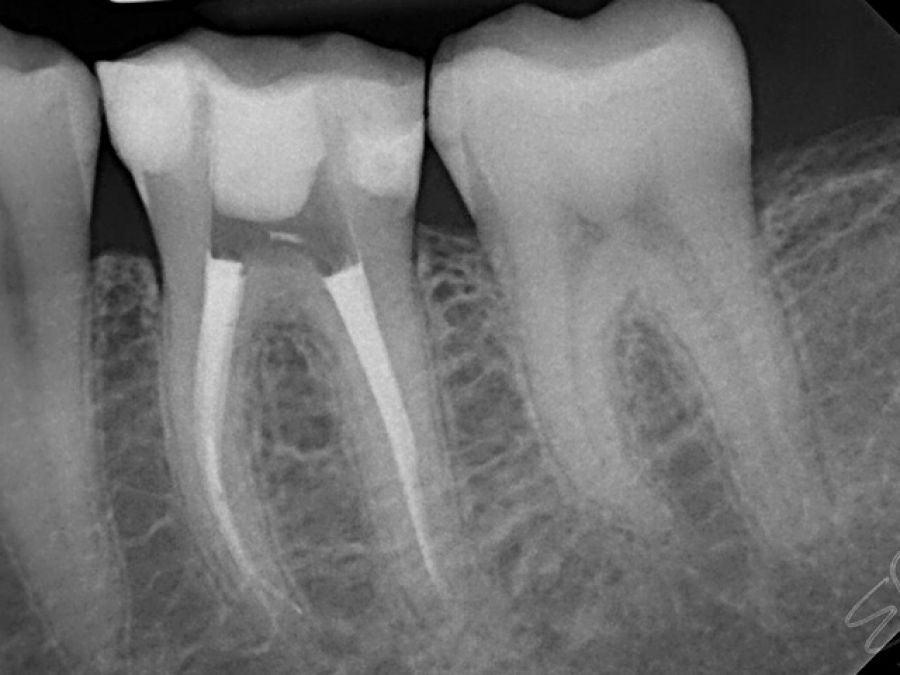

Kanal Tedavisi

Diş kökünün içerisinde, halk arasında ‘dişin siniri’ olarak bilinen, dişi besleyen bir damar-sinir paketi bulunmaktadır.

Tedavi edilmemiş çürükler nedeniyle bu dokunun hasarlanması ve/veya iltihaplanması durumunda, dokunun uzaklaştırılıp, kök kanalının şekillendirilmesi, temizlenmesi ve ardından kanalın dolgu maddeleriyle doldurulması işlemine kanal tedavisi adı verilmektedir. Bazı durumlarda kanal tedavisinin başarısını arttırmak amacıyla lazer destekli tedaviler yapılabilmektedir.